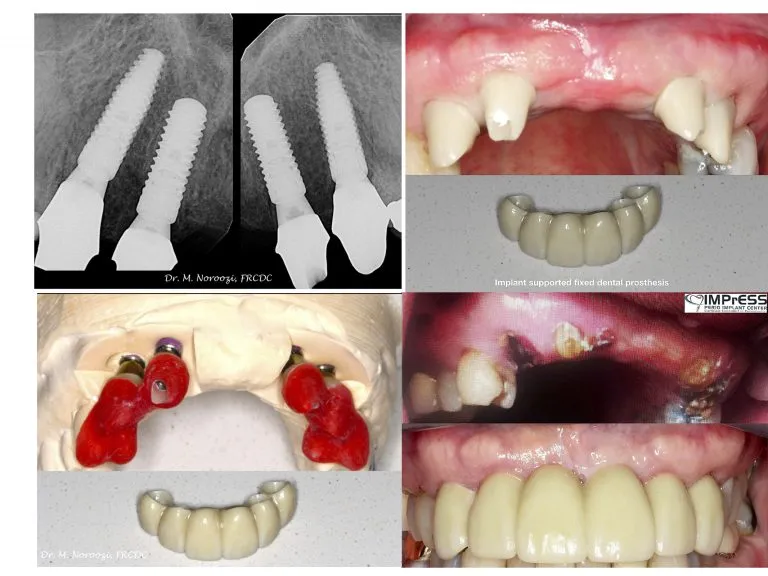

Failing Dental Bridge Being Replaced by Dental Implants